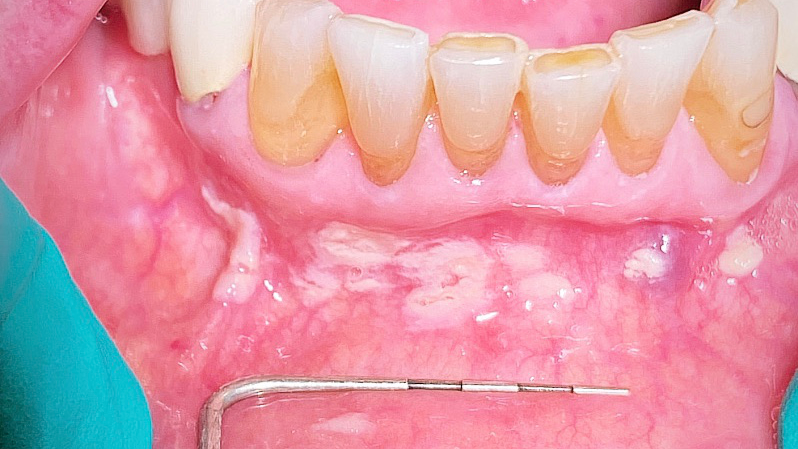

Take a look at the initial photograph. What’s the first thing that comes to your mind? Scattered, white, creamy patches in the lower anterior vestibule, each measuring approx. 3–6 mm (figure 1). Now, take a look at the second picture after the white patches were easily wiped off with gauze (figure 2). Note the red, thin membraned tissue? It was very tender to the touch.This diagnosis should be a slam dunk by now. Yup, you guessed it. Good ol’ pseudomembranous candidiasis, aka thrush.

- Acute pseudomembranous candidiasis consists of creamy, loose patches of desquamative epithelium that are easily removed.1 Red tissue tender to the touch is what is painful to the patient.